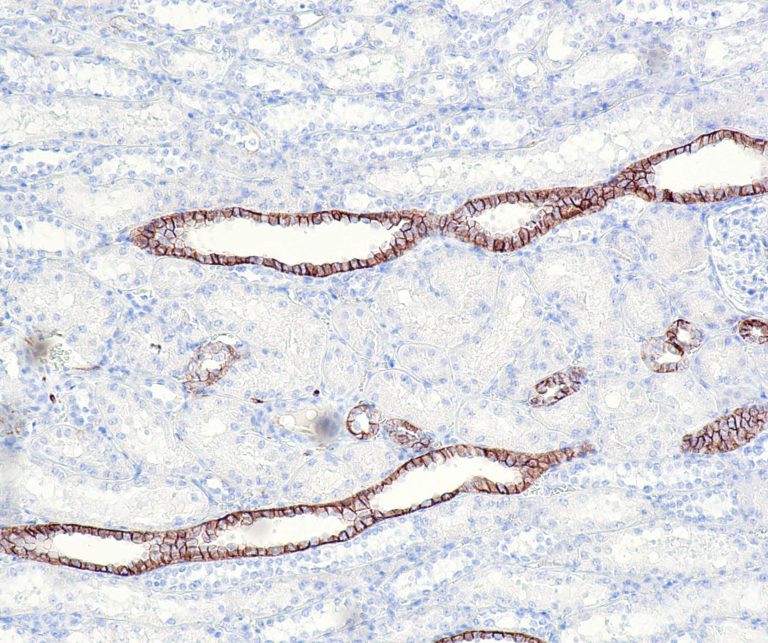

Vascular Pathology

Gastrointestinal (GI) Pathology

General Marker

Breast Pathology

Endocrine Pathology

Gynecological Pathology

Neuropathology

Infection Markers

Lung Pathology

Urinary Tract Pathology

Transplantation Pathology

Soft Tissue Pathology

Hematopathology